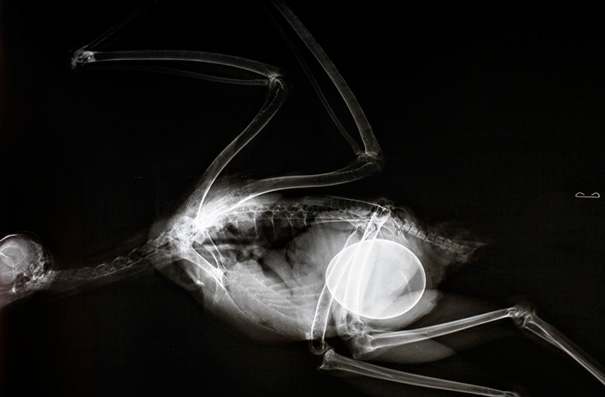

X-Ray Of Pregnant Bat

Why is it on one side. I'm not sure but it looks like it's bulging out the right not front.

This is normal. Any woman who has been pregnant can attest that sometimes the baby (or babies) will lay on one side. Can look pretty funny too! Have to remember there's also a lot of amniotic fluid around the baby which fills up the space so while it may look like the baby is smack in the middle it's often not.

Pregnant Bat's X-Ray

X-Ray Of A Pregnant Bat